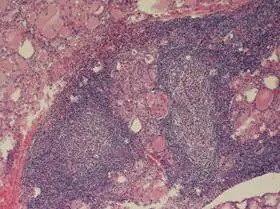

題目附圖為甲狀腺的 H&E 染色組織切片(低倍率),具有以下關鍵病理特徵:

- 淋巴細胞浸潤(Lymphocytic infiltration):影像中可見甲狀腺組織被大量的藍色發炎細胞(淋巴球)浸潤。

- 生發中心(Germinal centers):這是本題影像最顯著的特徵。在藍色的淋巴浸潤區域中,可見圓形、中心較淡的構造,這就是淋巴濾泡(lymphoid follicles)形成的生發中心。這代表長期且強烈的自體免疫反應。

- 甲狀腺濾泡萎縮(Atrophic follicles):正常的膠體(colloid)充滿的濾泡被破壞、變小或消失。

- Hürthle cell 變化:雖然在低倍下較難看清細胞細節,但在橋本氏甲狀腺炎中,殘存的濾泡細胞常發生嗜酸性變化(細胞質變紅、顆粒狀),稱為 Hürthle cells(或 oxyphil cells)。圖中粉紅色區域即為殘存或化生的甲狀腺濾泡上皮。